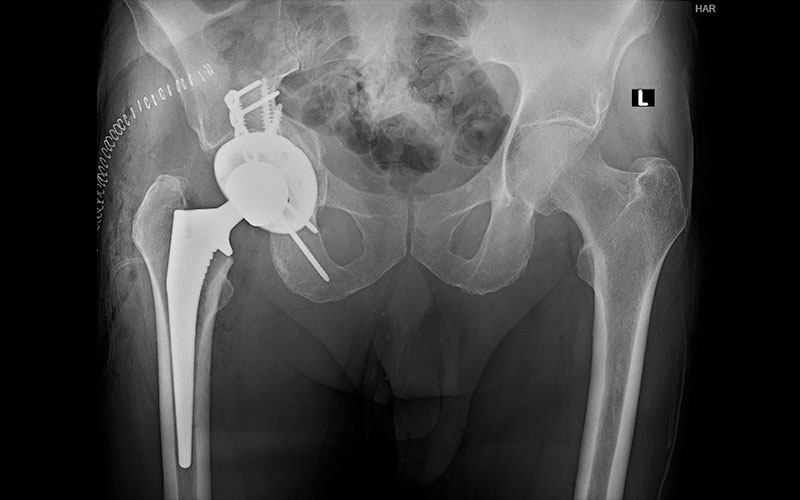

xray of surgical treatment for geriatric acetabular fracture

Patient who underwent surgical treatment of a geriatric acetabular fracture.